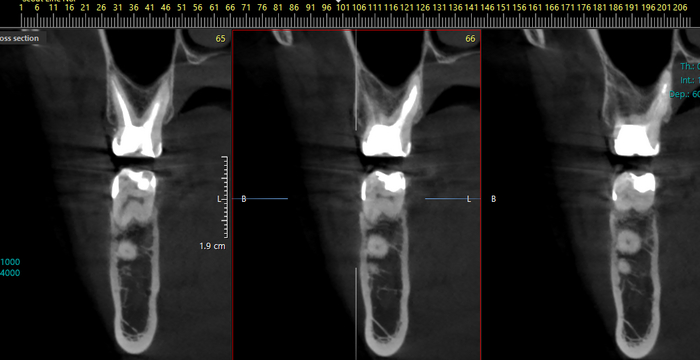

на снимке ниже первое кт от марта + пломбировка каналов до марта, её делали году в 2010-11 на обоих зубах

На 3 день боли пошел в первую попавшуюся хорошую по отзывам клинику, лечение 7ки прошло без осложнений, боль стихла на 2 сутки и дальше тишина, красота. Кальцит был в зубе 2 недели, при этом после первых 2 дней вообще перестал беспокоить, я успокоился, доктор сказал после полного восстановление зуба и удаления лекарства ждать полгода, но лучше поставить коронку типа временную, потом постоянную, так и не сделал до сих пор, зуб в прекрасном состоянии, воронка затянулась, вот снимок 7ки месячной давности после лечения.